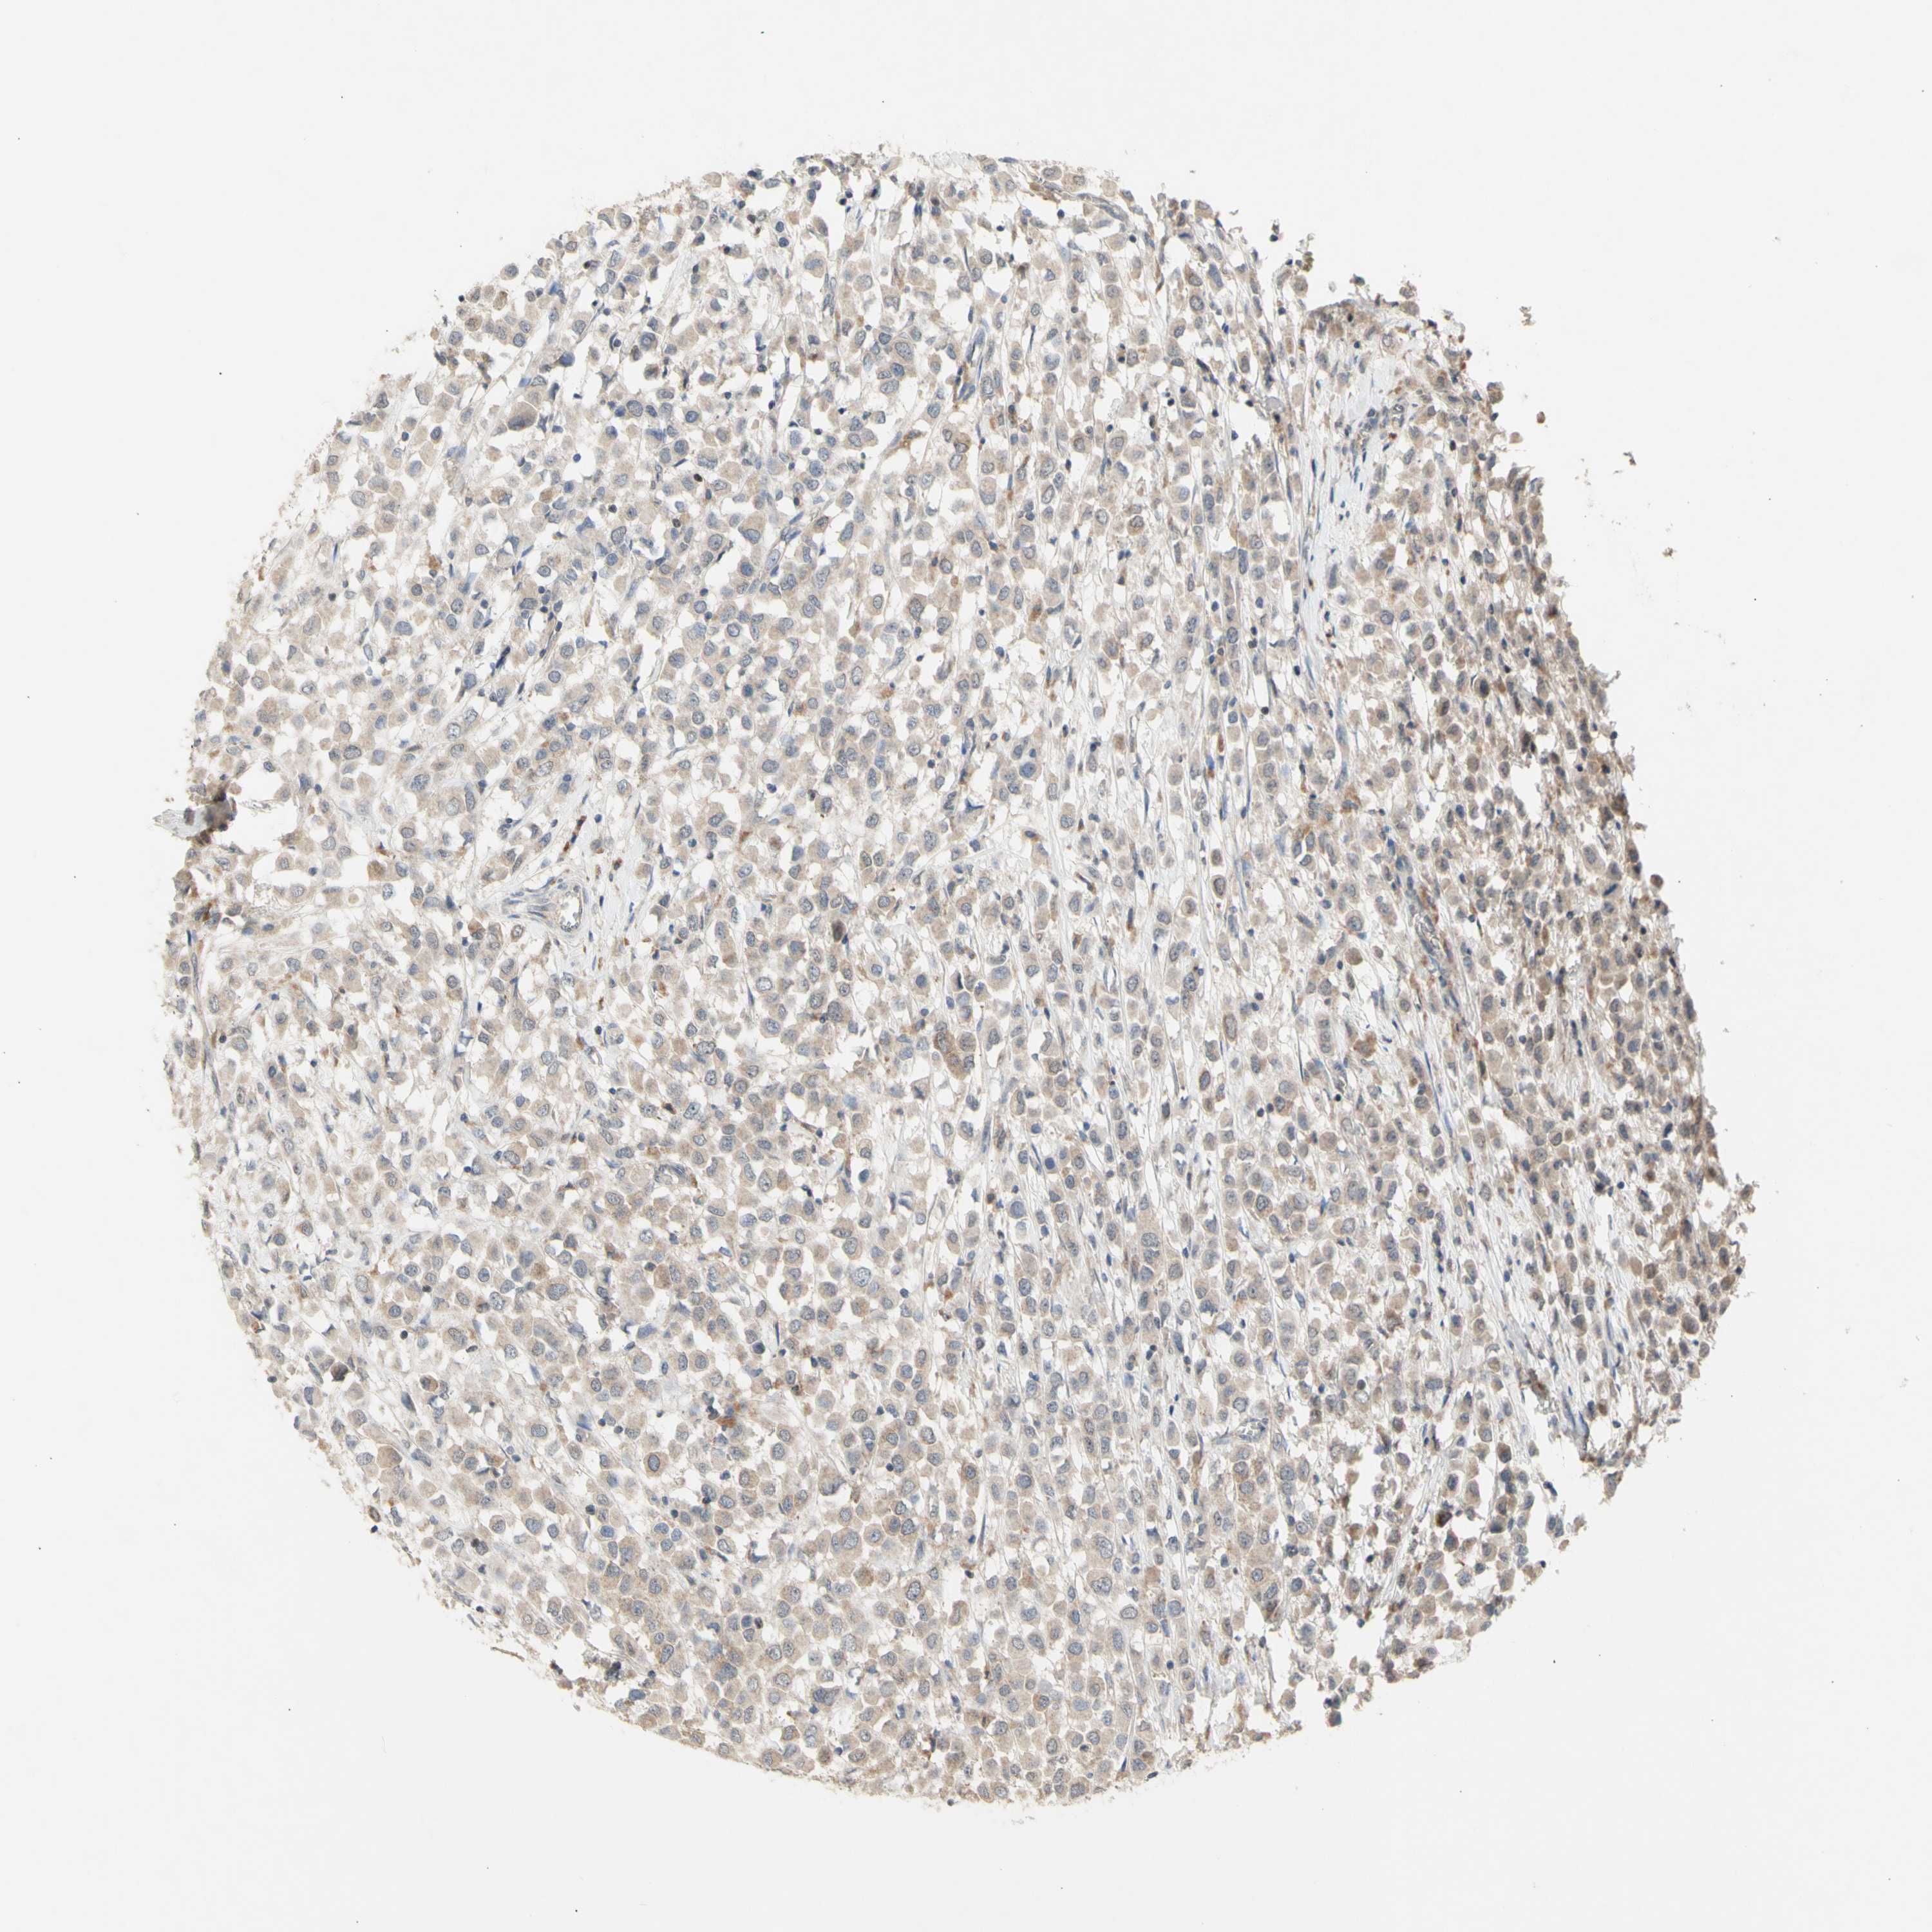

CANCER BREAST CANCER Show tissue menu

BRCA TCGA BRCA VALIDATION PROTEIN EXPRESSION